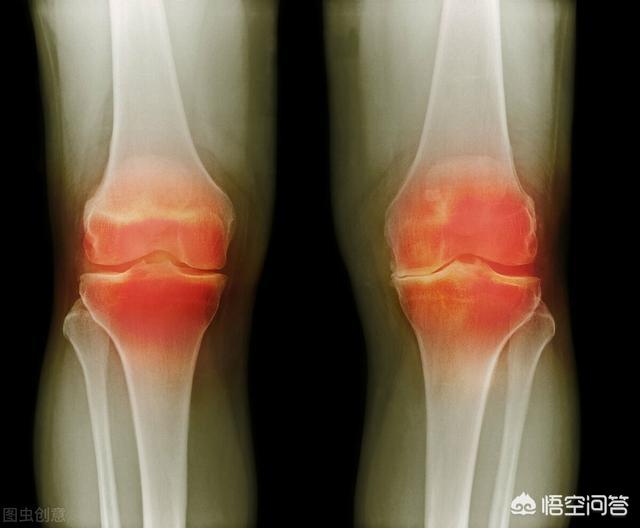

关节间隙为何会变小,多为大腿内外侧肌群病态后痉挛牵拉膝关节内外侧软组织所致。膝关节两边软组织受到向上牵拉影响,就会减小膝关节腔隙,使得膝关节腔内空间变小,微循环受阻,就会发生积液水肿现象,腔内压力就会变大,膝关节肿胀感,腔内各组织就会水肿,在人体运动中加速研磨就会加速受损,随着时间进展,病理演变开始从轻到重,腔内各组织水肿加速研磨逐渐不能负担起人体正常活动,在活动中就容易受到量变到质变的损伤,积液、滑膜炎、软骨磨损、韧带损伤、半月板损伤等等,这些都是关节腔内组织的病态。如下图所示:

一些关节病,如半月板损伤、骨关节炎、软骨损伤、关节腔游离体等,也可导致病理性关节弹响。病理性的关节弹响往往还伴随关节疼痛等症状,年轻人要考虑是否有关节创伤,中老年人则要警惕骨关节炎。骨关节炎的关节弹响是怎么出现的?健康关节中有关节软骨充当缓冲垫,避免骨与骨的直接摩擦,骨关节炎患者软骨磨损破坏甚至脱落,粗糙的骨端直接摩擦就会发出低沉的“咔嚓咔嚓”摩擦音。

骨关节炎的诊断需要临床症状与影像学表现相结合,从影像学上发现增生的骨赘后,还要看是否有临床症状。而骨质增生者,有些即便骨刺很大,却没有对关节周围组织、神经和血管产生挤压和摩擦,没有炎症和疼痛出现,就不能判定为骨关节炎。